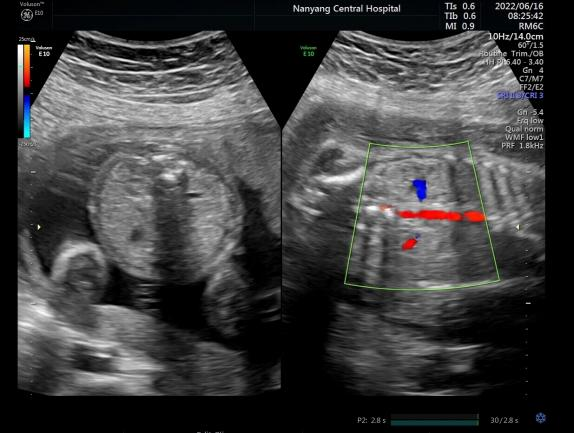

彩超是彩色多普勒超声的简称,是在B型超声的基础上,增加了彩色多普勒技术,用红色、蓝色及其亮度来显示人体组织的血流方向及速度,进一步显示目标部位的血流供应情况。当彩色多普勒功能开启的时候,图像上会出现星星点点的红色或蓝色的血流信息,称之为“彩超”。但彩色多普勒功能并不是时刻都启动的,黑白的二维图像是基础,只有基础图像清晰,才会在有需要的情况下开启“彩超”,可以更好地进一步观察目标结构,所以,“彩超”大部分时间是黑白的。

左图“黑白”,右图“彩色”